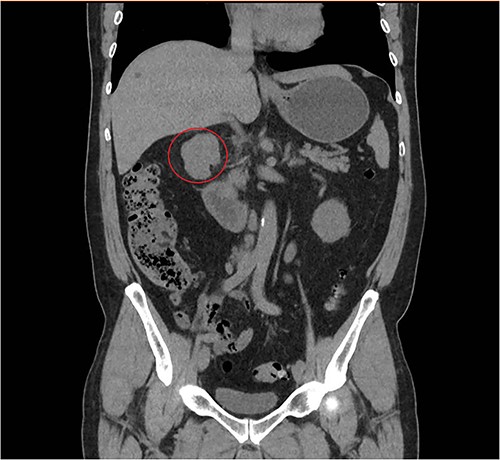

A 57-year-old male, with only a history of severe arterial hypertension, was admitted to our surgical department because of a retroperitoneal nodular mass measuring about 4 cm in maximum diameter, discovered on an abdominal echography. The ultrasonography was performed for the onset of a 1-year long vague abdominal pain at the right hypochondrium with posterior irradiation, without any other associated symptoms. Subsequently, he underwent total body enhanced CT scan, which confirmed the presence of a retroperitoneal polylobate neoformation developing in the right perirenal space, with maximum axial diameters of about 40 × 70 mm, which exerted a mass effect on the duodenum with which a thin adipose cleavage plane was present (Figs 1 and 2). The mass was rich of contrast impregnation in the early phase, which further increased in the portal phase. The presence of a vascular structure was highlighted posteriorly to the mass.

Coronal abdominal CT scan revealing a retroperitoneal polylobate neoformation near the duodenum.